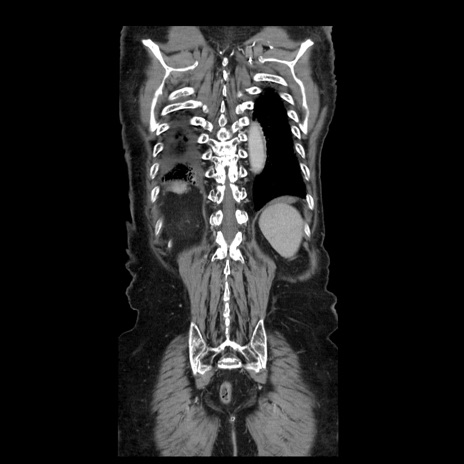

横断像

症例21(冠状断像)

【症例】70歳代男性

【主訴】腹痛

【現病歴】肝硬変・肝細胞癌にてかかりつけの方。約9時間前に食後より腹痛出現。症状が徐々に増悪し、嘔吐出現したため来院。

【既往歴】肝硬変、肝細胞癌(RFA、TACE後)

【身体所見】意識清明、表情苦悶様、BT 36℃、BP 129/78mmHg、P 88bpm、SpO2 97%(RA)、右上腹部から心窩部にかけて圧痛あり、反跳痛なし、筋性防御あり。

【データ】WBC 5800、CRP 0.16